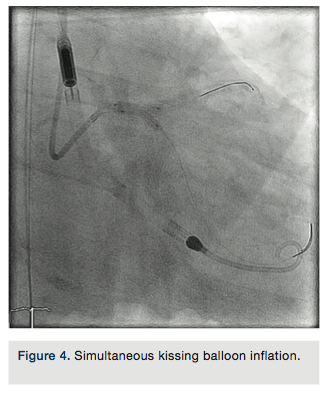

LAD guide wire was withdrawn and the LAD was rewired through the LM portion of the stent. A 3.5 x 15mm Sprinter balloon (Medtronic) was used to cross into the LAD and inflated at 18atm. A 3.5 x 12mm Resolute Integrity stent was deployed at the proximal LAD into the LM at 18atm. The LCX guide wire was pulled back into the guide catheter, and re-advanced into the LCX through the LM stent. Two 3.5 x 15mm NC Sprinter balloons were placed from the LM to the LCX and LAD, and a simultaneous “kissing” inflation was performed at 14atm (Figure 4). A 4.0 x 12mm NC Sprinter balloon was inflated in the LM portion of the stents at 18atm for proximal optimization. IVUS examination revealed excellent stent apposition (Figures 5a-5b). The stenoses in the proximal, mid and distal LAD were not treated. All catheters were removed except the Impella catheter, which was anchored in place using sutures.